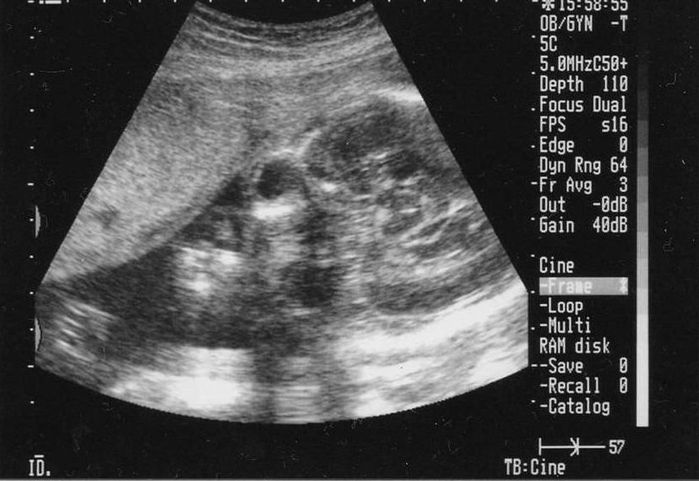

妊娠7週目のエコー写真

頭と体が2頭身に分かれました。